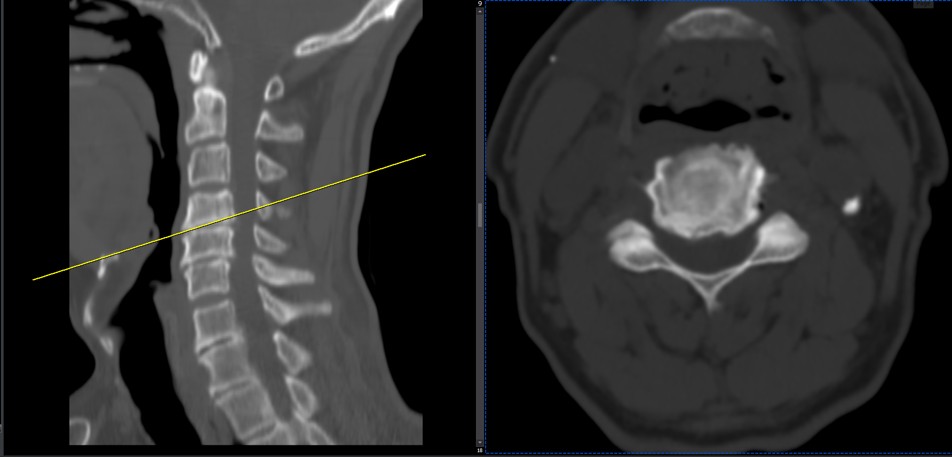

41 years old man presented to my clinic in October 2023 with acute and sever R neck pain with radicular pain to his R upper extremity along C6 dematom since 2 weeks ago. Examination didn’t show any upper motor signs. Was suggested urgent surgery

I ordered EMG/ NCV : showed mild R C6, C7 irritation without any active axonal loss

In his MRI was reported R. para R. IVF Massive extrusion. I decided to control his pain and manage this patient with reevaluation of patient every other session. For 5 sessions i just used acupuncture and laser and IFC and mild adjustments to his R. T3-T7 and mild arthosteem to above and below involved segment. Cervical adjustment considered contraindicated for this patient. From session 6th- 8th i started to use mild/gentle cervical decompression. He used soft cervical collar all the time. His pain decreased by 80 percent

I gave him cervical traction pump to be used 3-5 times per day at home for the next 3 months and i released the patient. He was evaluated every week once for one month and after that every 2 weeks. After 3 month I repeated MRI. Size of the herniated disc was reduced greater than 50 percent. Asked him to do another mri in 6 months

MRIs before and after proper management of this patient: